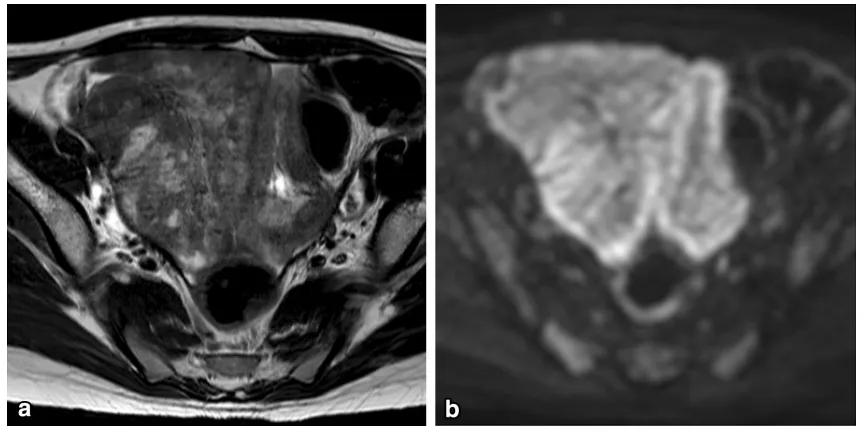

卵巢原发淋巴瘤罕见,常见组织学类型为弥漫大 B 细胞淋巴瘤及 Burkitt 淋巴瘤,后者常见于儿童及青少年。最常见的症状是腹部疼痛。原发继发影像表现一致,影像鉴别困难。常见表现为双侧卵巢实性肿物,T2WI 呈较信号均匀,内可见高信号分隔,增强扫描明显强化。肿物边缘多发线样排列的囊性结节,为「卵泡保留征」。

女,12 岁,卵巢 Burkitt 淋巴瘤。双侧卵巢肿物,T2WI 信号稍高(图 a),DWI 呈高信号(图 b),增强扫描明显强化(图 c),箭头显示肿物边缘多发囊性结节,为卵泡保留征。

女,34 岁,胃癌双侧卵巢转移瘤。T2WI 显示双侧卵巢实性肿瘤,T2WI 呈高低混杂信号(图 a),DWI 呈高信号(图 b)。